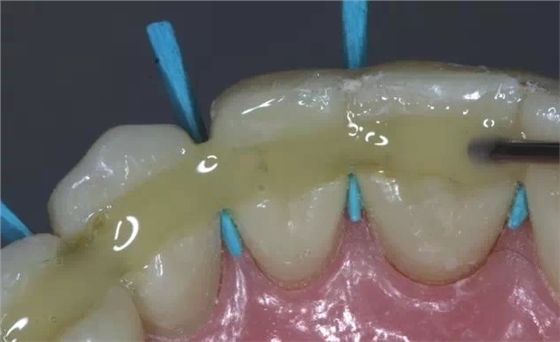

牙周炎發(fā)展到一定階段時(shí),僅采用基礎(chǔ)治療難以取得較好療效,必須通過(guò)適時(shí)而合宜的手術(shù)治療挽救患牙,才能保持牙周組織健康,延長(zhǎng)患牙在口腔內(nèi)的壽命,維持牙列的完整性,促進(jìn)全身健康。其手段包括齦下刮治、根面平整、牙周翻瓣術(shù)、牙齦切除術(shù)、牙周夾板固定術(shù)等。